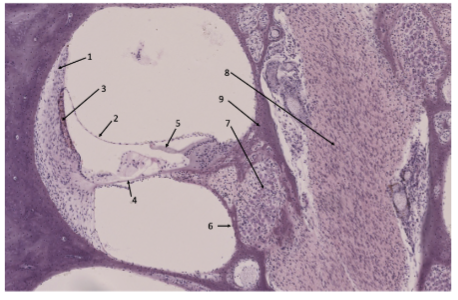

a) Vilken siffra pekar på strukturen som separerar scala media från scala vestibuli ? (1..9)

b) Vilken siffra pekar på nervcellerna (somat) som innerverar hårcellerna? (1..9)

a) 2

b) 7